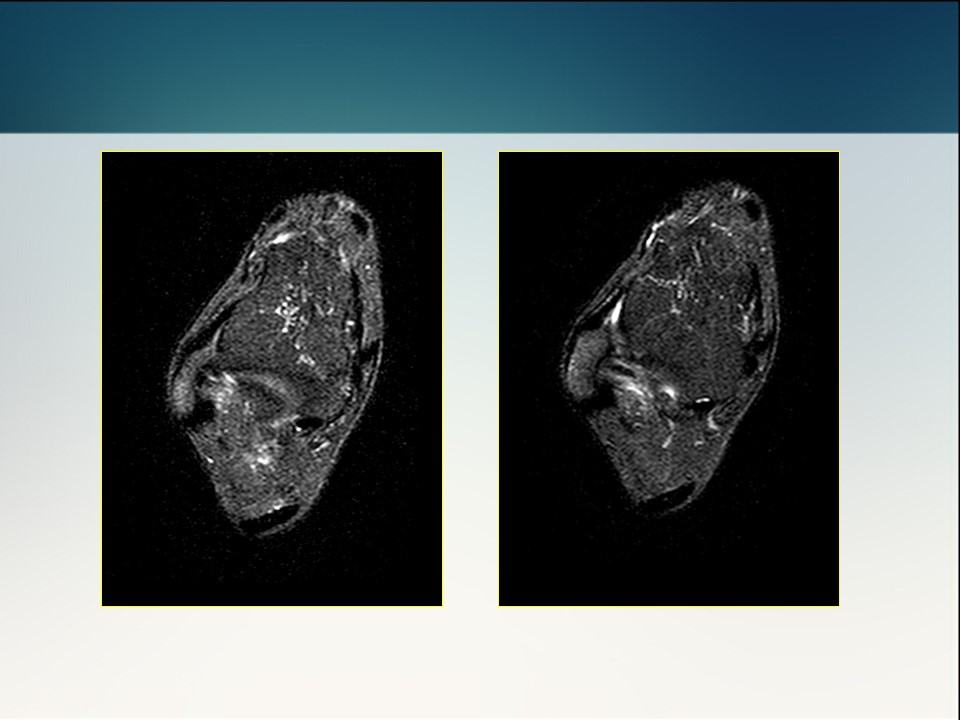

半月板损伤术前及修补术后MR影像学评价